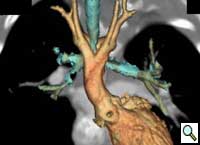

Patient was further evaluated with 64-slice MD CT angiogram which revealed double aortic arch, with balanced arches encircling the trachea and esophagus (Figure 1). The distal trachea and proximal left bronchus were compressed by the vascular ring (Figure 2, 3).